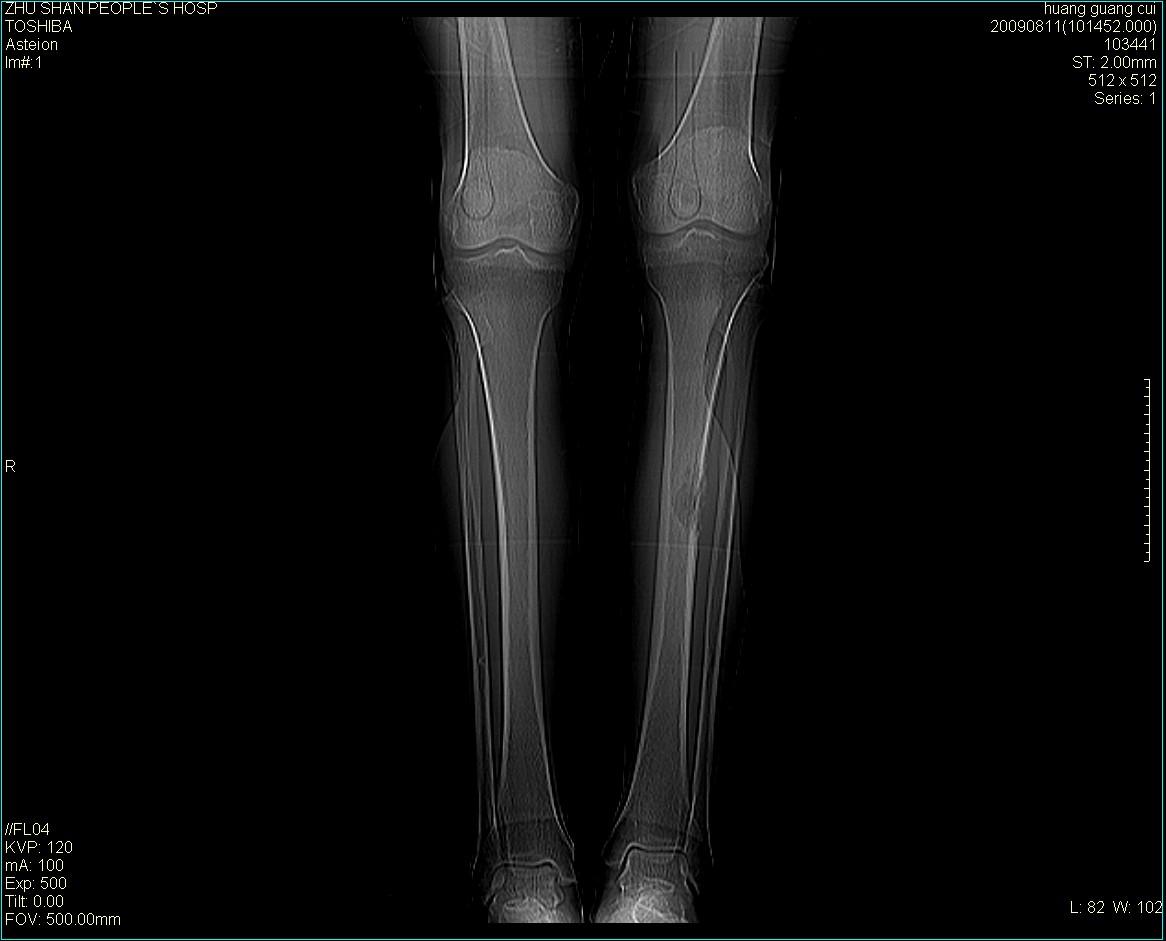

标题: CT21557:女性 56岁 左胫骨中断肿痛2月余。 [打印本页]

标题: CT21557:女性 56岁 左胫骨中断肿痛2月余。

女性 56岁 左胫骨中断肿痛2月余。转移瘤or尤文氏肉瘤?

左侧胫骨中段骨皮质溶骨性破坏,髓腔内外见软组织肿块,无明显钙化及成骨,定位相显示病变周围“筛孔样”改变,定性恶性无疑,原发或转移均有可能,倾向于骨纤维肉瘤可能性大,转移瘤不排除。膝关节以下骨转移很少,且要有原发灶支持,尤文氏肉瘤年龄太大不支持。